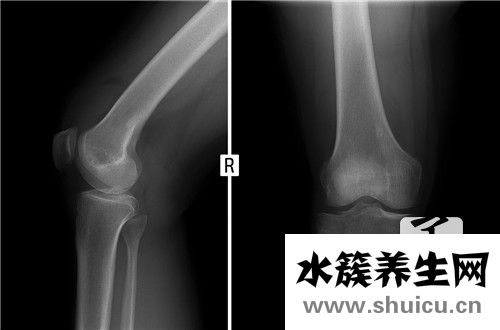

骨髓水腫是一種副作用大的疾病,以骨培養基質水腫為主。雖然這種疾病的原因尚不確定,但它可能與創傷和生長激素密切相關。根據臨床醫學的實際效果,MRI 治療效果非常好,一般患者3-6個月就可以完全康復...